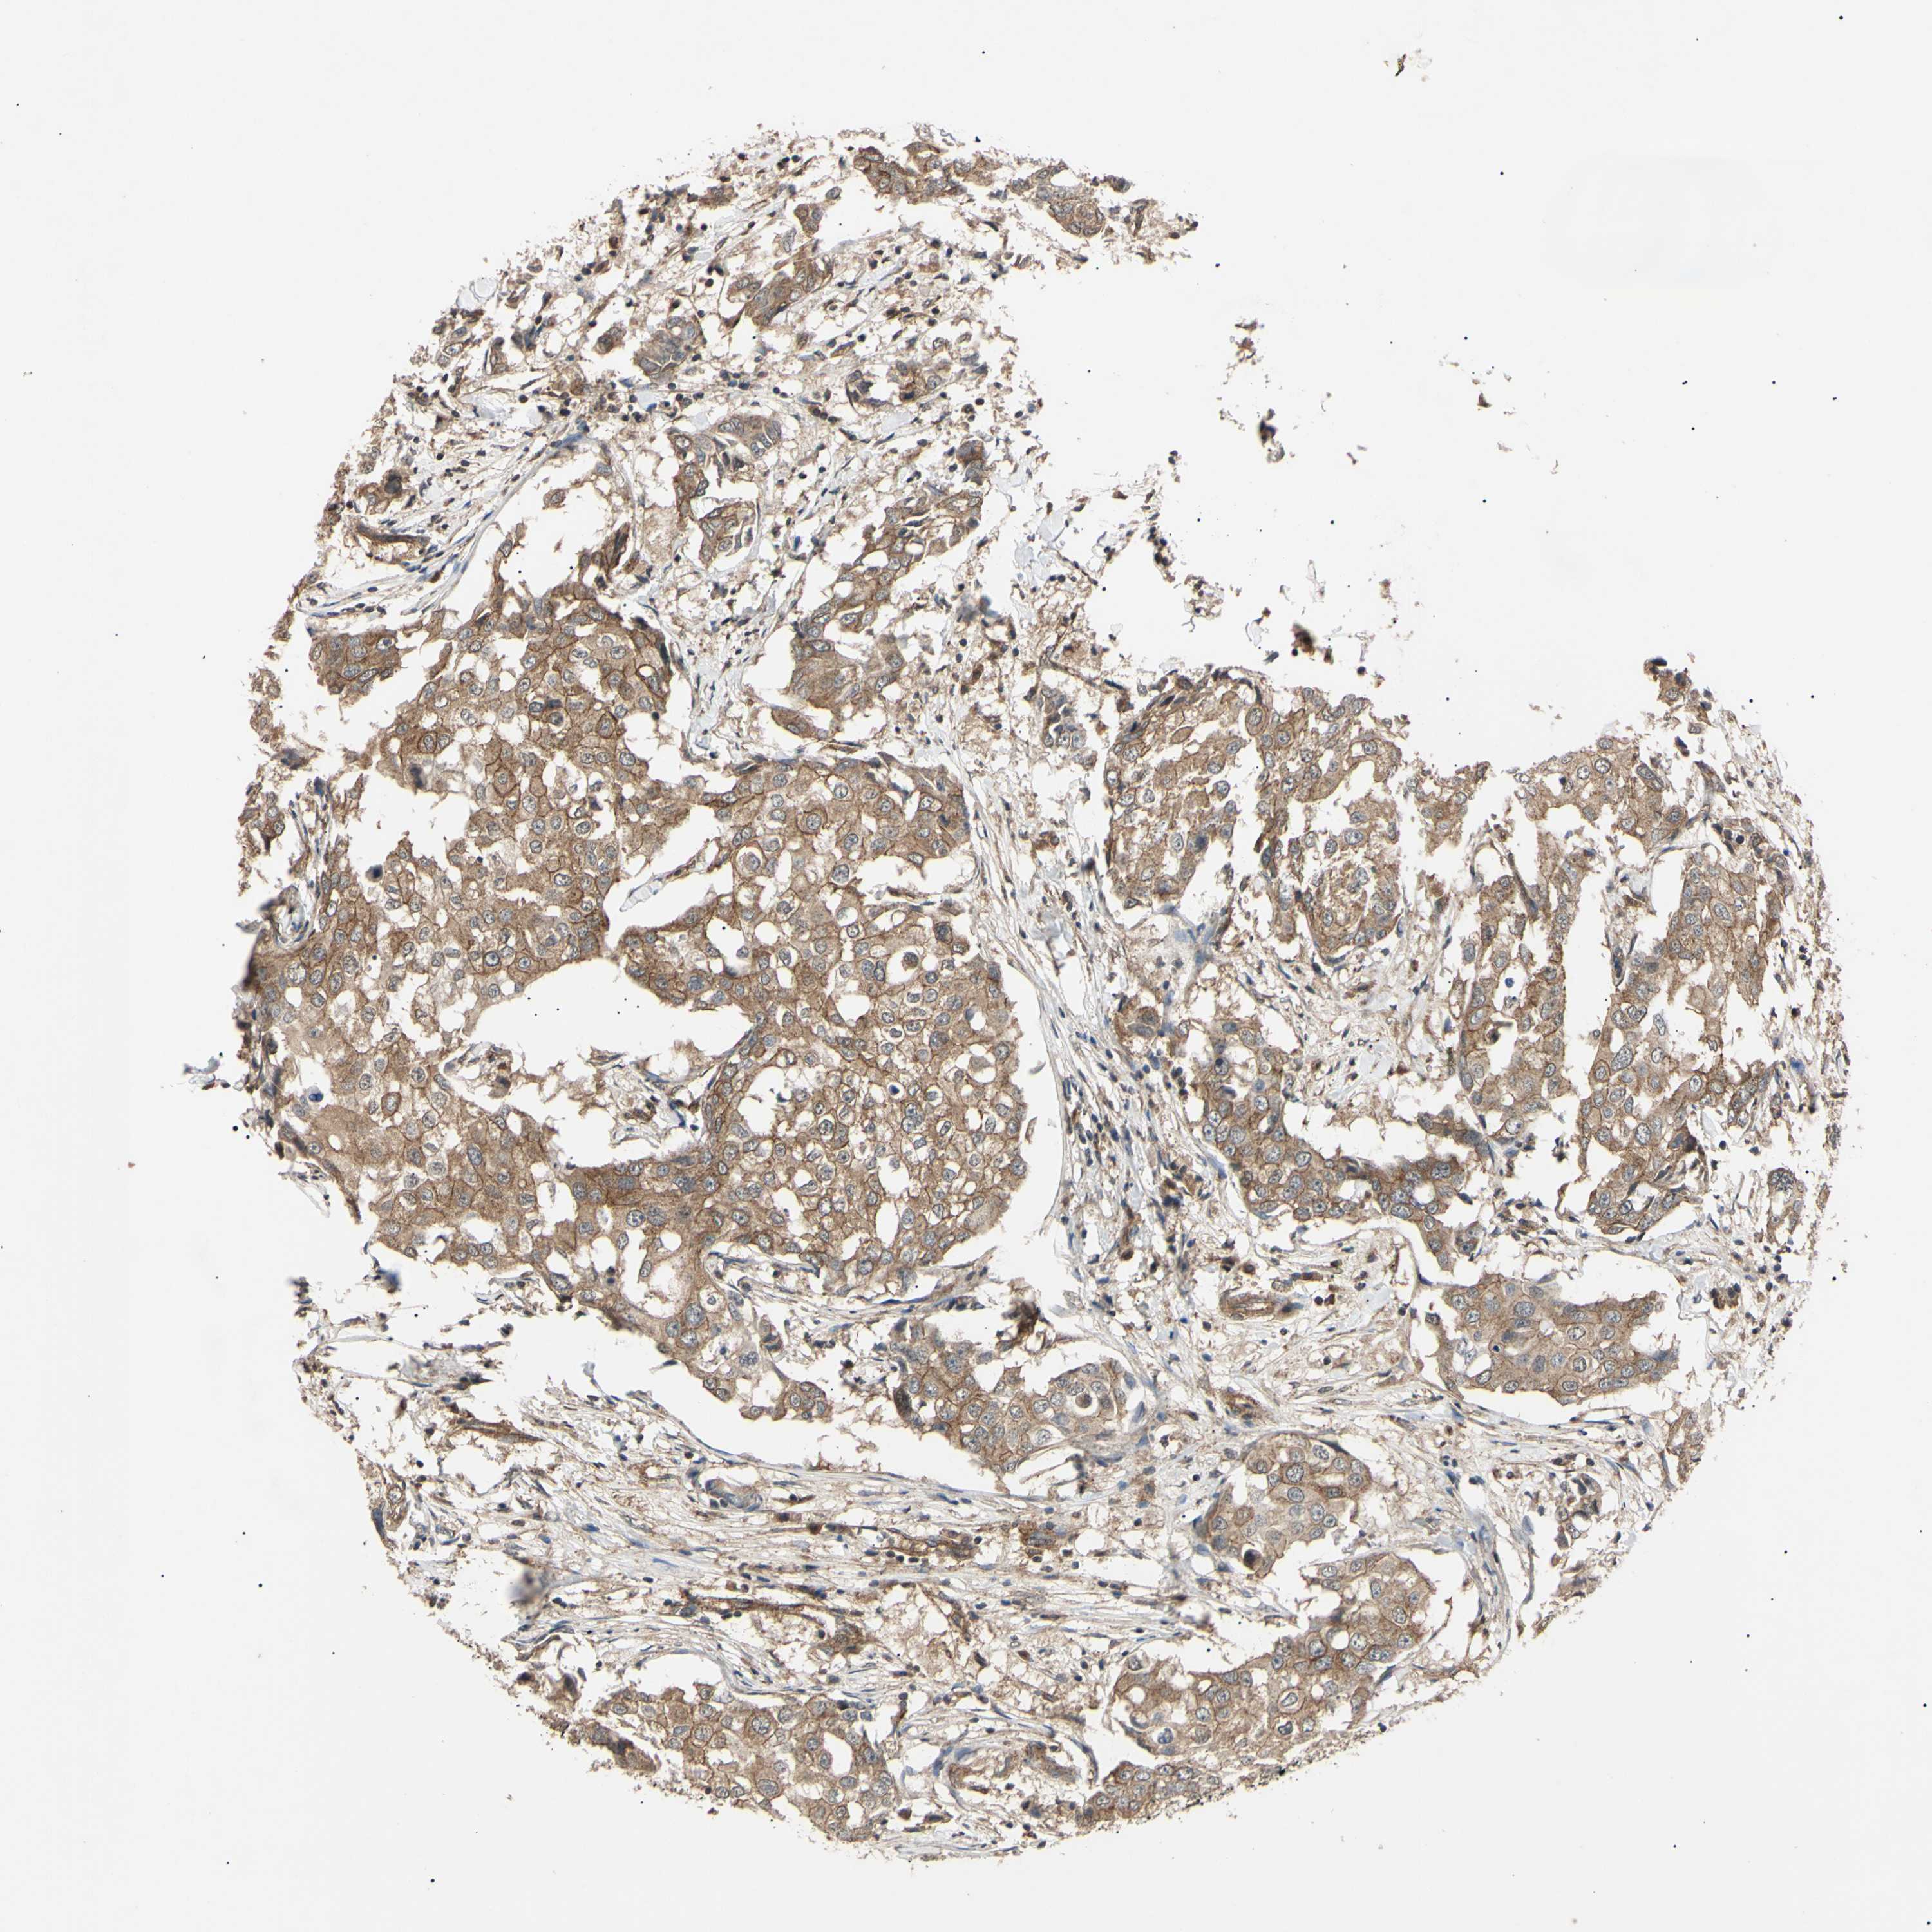

CANCER BREAST CANCER Show tissue menu

BRCA TCGA BRCA VALIDATION PROTEIN EXPRESSION

Breast cancer

Human cancer